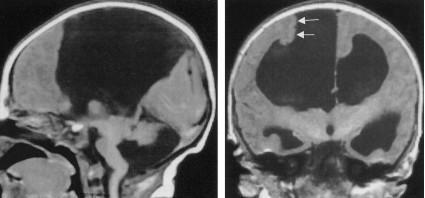

All 3 commissures are absent.

Cingulate gyrus (black arrows) “mirrors” the development of the corpus callosum.

Enlarged HC connects fornices, not cerebral hemispheres